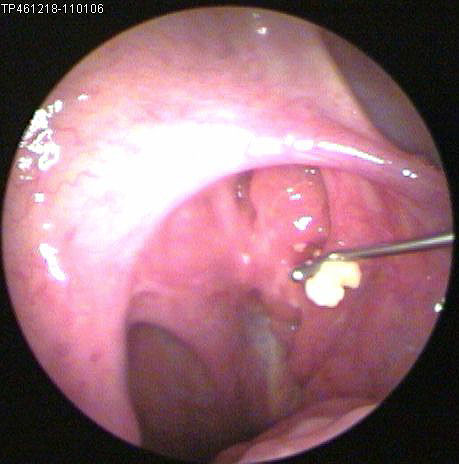

JFC Cauterización química de cabeza de vena de septum

JFC Cauterización de epistaxis con nitrato de plata.